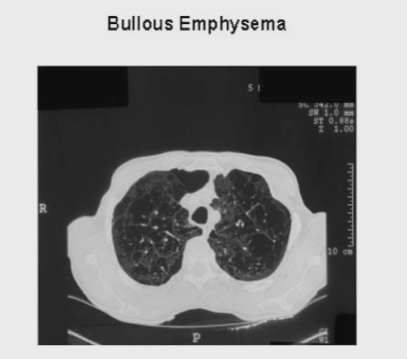

Emphysema is the abnormal enlargement of airspaces in the lung. Where does this occur?

• Abnormal airspace enlargment in emphysema happens distal to the terminal bronchioles - aka the damage starts right where gas exchange can take place

• CD8 lymphocytes, neutrophils, and macrophages - remember this inflamation will likely persist even after the person stops smoking

People with emphysema don’t have extremely inflammed airways and don’t have muscle weakness in their diaphragm. So why do they have trouble exhaling?

Loss of attachments between alveoli causes dynamic airway collapse in exhalation - (remember airway pressure drops at the edges as gas moves through)